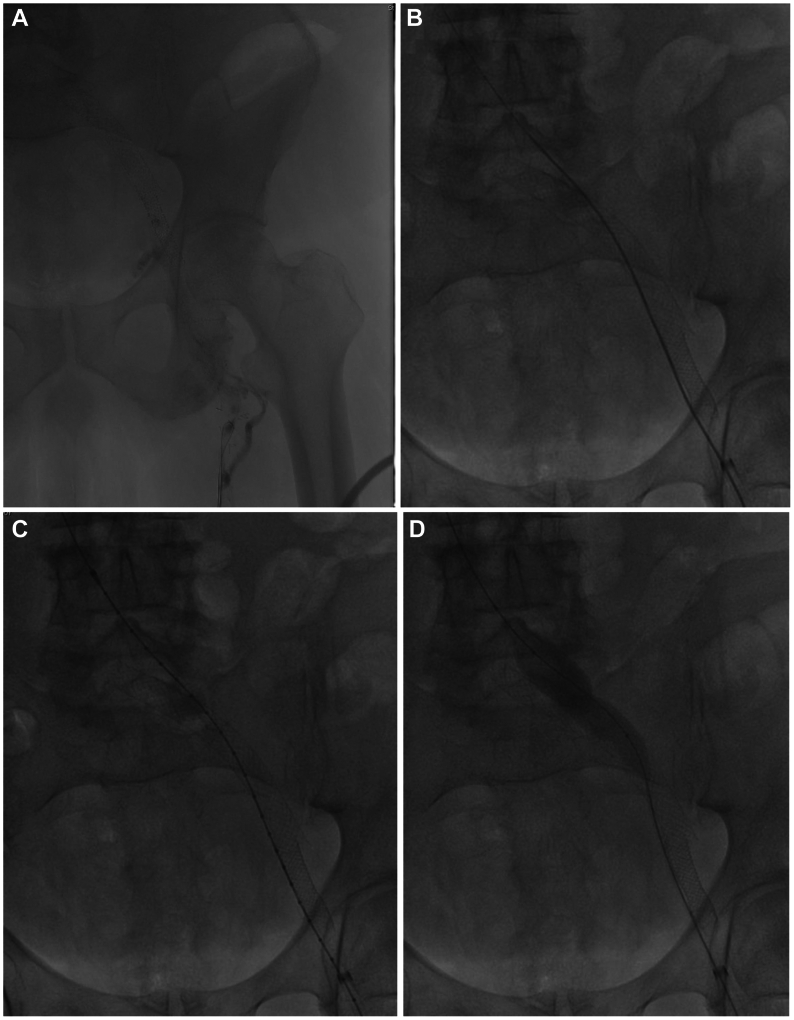

Fig 3.

(A) Initial venogram demonstrating an occluded iliofemoral venous stent; (B) Successful wire recanalization around the pre-existing stent; (C) Intravascular ultrasound (IVUS) confirmation of entry into caudal inferior vena cava; (D) Sequential angioplasty of endobypass tract; (E) Fluoroscopic image depicting the configuration of the original stent and the new conduit around it. (F) Completion venogram depicting a patent endobypass conduit of Wallstent-Z stent combination with orange arrow depicting the occluded original stent column.